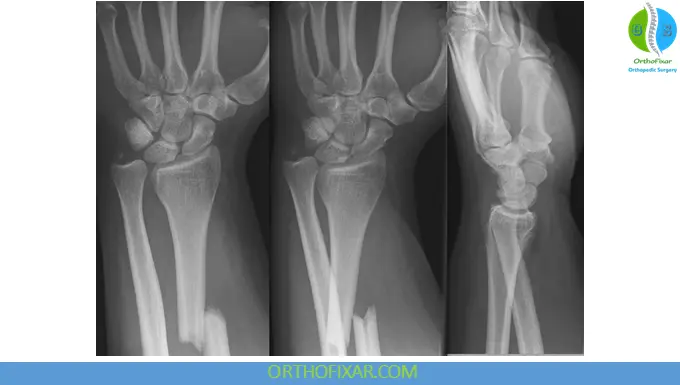

Diagnosis

Imaging

- Plain X-rays (AP & lateral views) of the forearm and wrist

- Key findings:

- Radial shaft fracture

- DRUJ widening or displacement

Failure to assess the wrist joint is a classic pitfall.